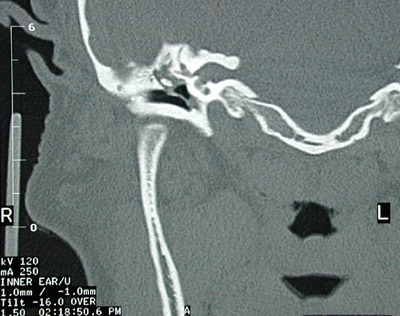

| The axial CT scan view of the head on the right seen above reveals a soft tissue density within the middle ear cavity that was associated with thickening and retraction of the tympanic membrane and abnormal soft tissue in the epitympanum with extension superiorly. A closer view is seen below. |